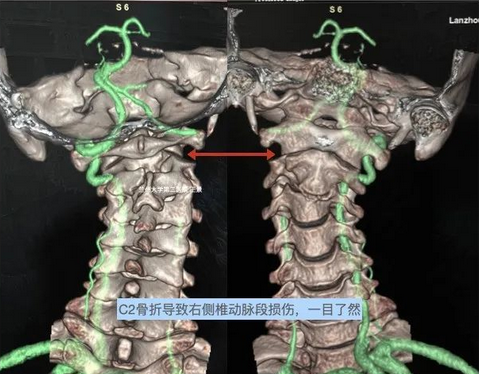

颈椎骨折导致椎动脉损伤!